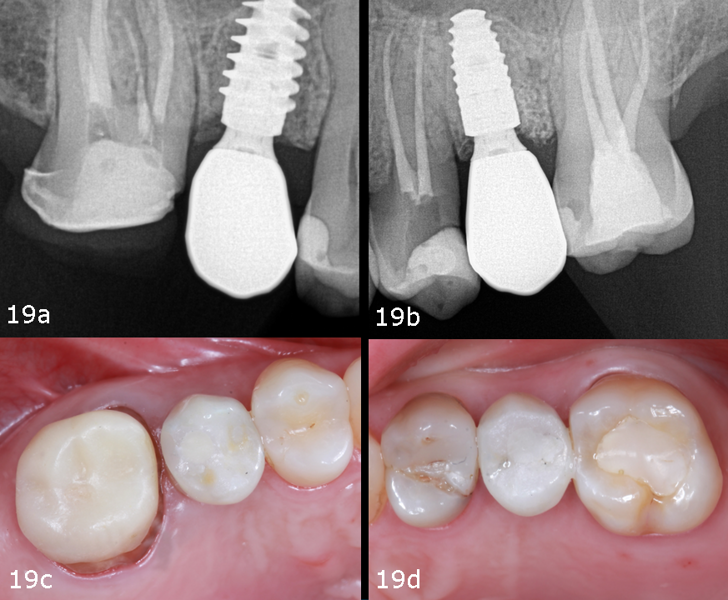

The surgical guide was inserted and verified for accurate fit. Osteotomy preparation was carried out according to the protocol generated by coDiagnostiX (Dental Wings), tailored to the planned implant types on each side (Figs. 8a–g). The Straumann BLX implant was placed into site #15, achieving primary stability at 30 N cm. The Straumann BLC implant was inserted into site #25, reaching primary stability at 50 N cm (Figs. 9a–g).

The treatment process and outcomes exceeded the patient’s expectations, in that the total treatment time was only 65 days and she experienced no discomfort throughout the process. At the one-year follow-up appointment, new photographs and radiographs were taken, revealing healthy and stable soft and hard tissue (Figs. 19a–d).